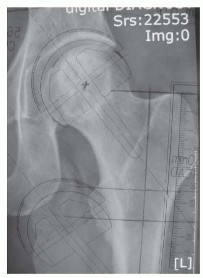

DEFINITION Hip resurfacing is a surgical procedure whereby the femoral head is preserved and a component (mos…